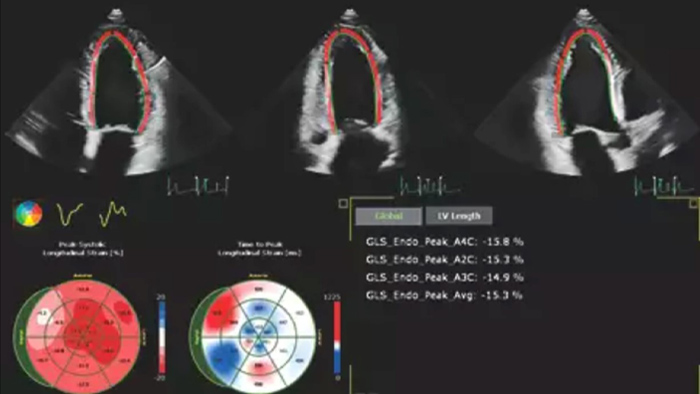

Echo is often the first cardiac imaging test that’s performed for patients with suspected heart failure. An echocardiogram gives us a wealth of information on cardiac structure and function using both 2D and 3D tools. Echocardiography can help us understand the etiology of heart failure in many situations. I routinely use information derived from both 2D and 3D analysis and strain to better understand my patients. AutoStrain, Dynamic HeartModel and Auto RV are invaluable tools that are used both in the diagnosis and surveillance of patients with heart failure.”

Fast and reproducible tools with integrated workflows

Robust and reproducible imaging tools are important to diagnose and monitor disease progression in heart failure. Current guidelines support the use of advanced echocardiography tools such as longitudinal strain and 3D assessment of LV and RV volumes and function.

Automation for robust, proven reproducible cardiac quantification in both 2D and 3D.